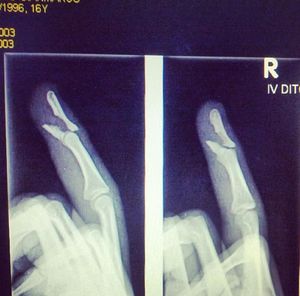

Dx and treatment of this kind of fracture? 16 y/o, M, basketball player, he dunked and remained stuck to the net. What's your diagnosis, management and treatment for this kind of fracture? What would the complications be? Will he be able to play again?